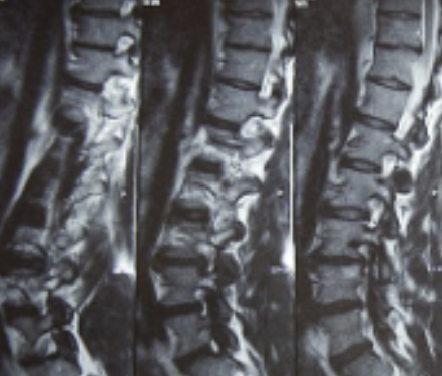

허리디스크는 디스크가 터져서 신경을 누를 경우 생기는 것으로 보통 4,5번에서 많이 발생하고 디스크가 터진 양이 적다면 터진 순간부터 수분이 날아가면서 양이 많이 없어지는데 그렇지 않고 양이 많을 경우 극심한 통증이 생깁니다.

허리디스크를 정확하게 진단하기 위해서는 엑스레이로는 힘들며, MRI를 통해 검사해야 정확하게 볼 수 있습니다.

MRI가 몸에 좋지 않지만 허리 통증으로 엑스레이만 진행할 경우 오진이 많아 지속적인 통증이 계속된다면 허리디스크를 의심하고 MRI 검사를 한번 받아보시길 권유드립니다.